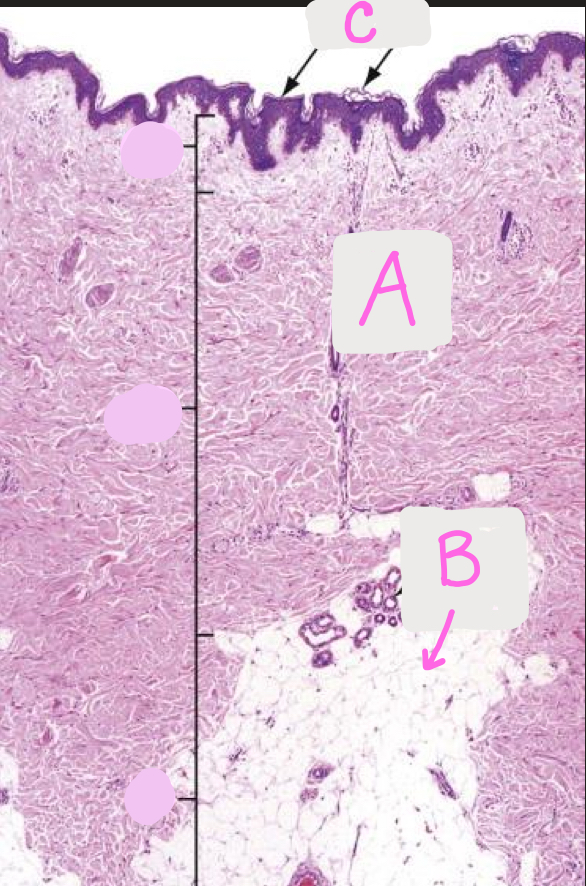

Identify each layer of the skin (A-C)

A. Dermis

B. Hypodermis

C. Epidermis